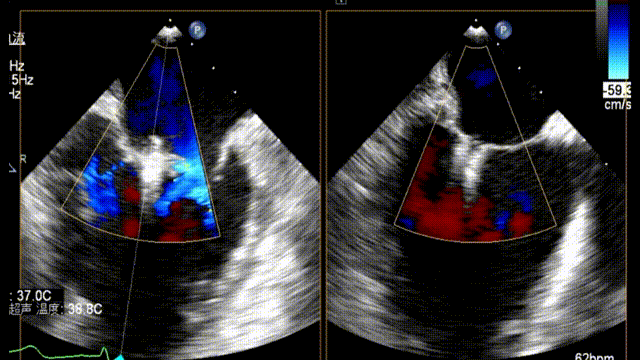

术前TEE显示重度功能性二尖瓣反流,反流位于A2/P2;